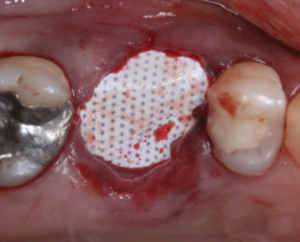

Vista oclusal do alvéolo selado pela membrana Cytoplast .